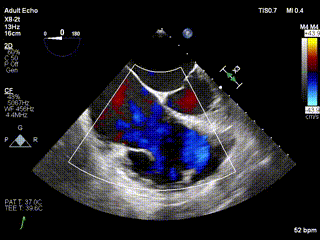

2021年12月24日,復旦大學附屬中山醫院葛均波院士團隊成功應用LuX-Valve Plus為一例極重度三尖瓣反流(TR)合并房顫、房缺的患者完成了經血管三尖瓣置換術,這是在前基礎上,本周完成的第三例經血管三尖瓣置換手術,葛均波院士、周達新教授等與心外科魏來教授、賴顥教授,心超室的潘翠珍教授、李偉教授及麻醉科的郭克芳教授共同完成了本周手術,均獲得圓滿成功!患者術后超聲顯示無TR,臨床癥狀明顯改善。本周手術的成功也為LuX-Valve Plus救治性臨床研究添上了濃墨重彩的一筆。

三例患者入院后,葛均波院士團隊周達新教授、潘文志教授、張源博士、陳莎莎博士及心超室的潘翠珍教授、李偉教授對患者的情況進行詳細評估和討論,最終決定為三例患者選擇LuX-Valve Plus40mm、50mm和50mm型號的瓣膜進行手術治療。手術后即刻拔除氣管插管,術后患者三尖瓣反流癥狀得到顯著改善,復查心超結果顯示人工三尖瓣瓣膜支架固定穩定,瓣葉關閉形態未見異常,未見明顯反流。

LuX-Valve Plus是LuX-Valve系列產品的第二代,采用的是經血管入路的全新輸送系統,其設計開發過程得到了上海中山醫院葛均波院士及其團隊的精心指導,研究結果提示瓣膜植入的安全性和有效性俱佳,尤其瓣膜獨特的設計使其具有極佳自適應性,本周三例患者病因及解剖結構各具特點,但均可從LuX-Valve Plus植入術明顯獲益。目前,LuX-Valve Plus已在全國各中心開展救治性臨床研究,相信未來定會為更多的三尖瓣反流患者帶來福音。